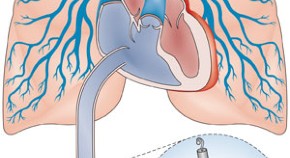

• Remote ischaemic conditioning has been extensively studied, and encouraging proof-of-concept clinical trial data have emerged. A study newly published in The Lancet takes the field an important step forward, demonstrating for the first time that remote ischaemic conditioning before CABG surgery reduces all-cause mortality.

• Robert Bell

• Derek Yellon